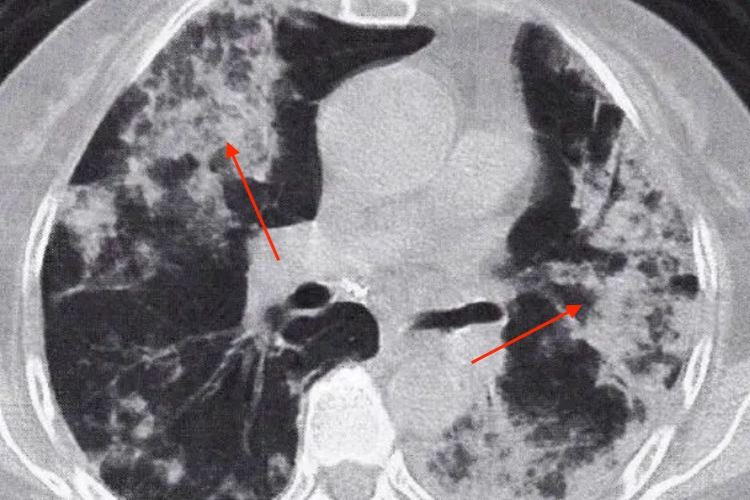

弥漫型

弥漫型肺癌表现为两肺弥漫分布的结节影,可伴有肺门、纵隔淋巴结增大;病变融合成大片肺炎实变影。其内可见“空气支气管征”,但其走行僵硬,呈“枯树枝样”改变,有时其中可见高密度血管影,称之为“CT血管造影征”。